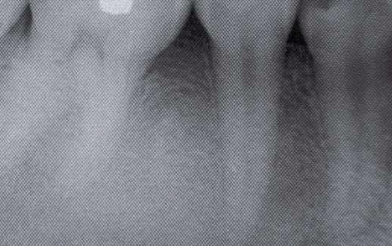

Periapical Cemento-Osseous Dysplasia lesions start out as completely radiopaque. True or False?

False, they start out as Radiolucent and become mixed and then end as radioopaque with a radiolucent rim.